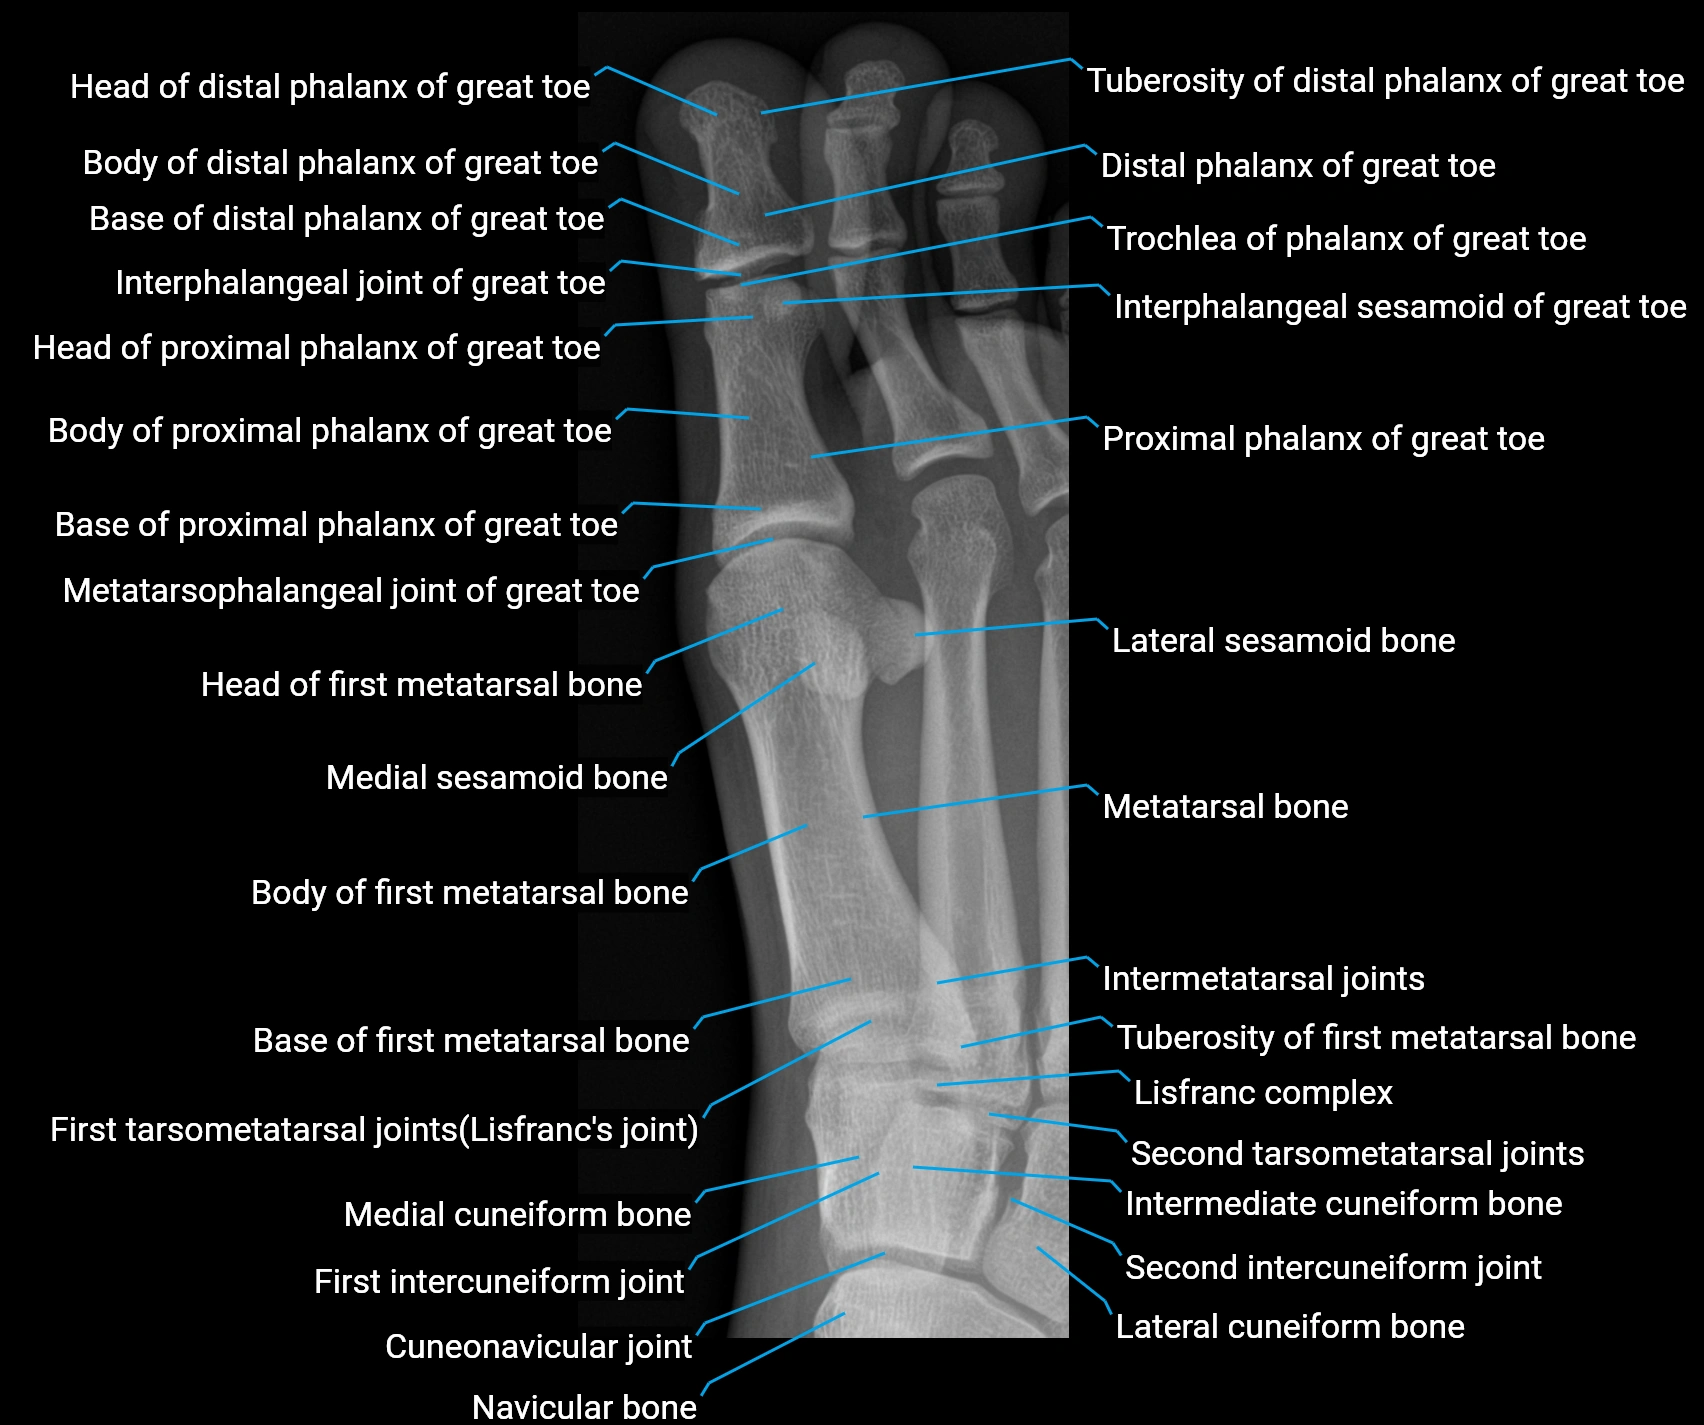

CT Appearance

Non-Contrast CT:

-

Muscle: homogeneous soft-tissue density lateral to calcaneus

Tendon: linear soft-tissue density running toward the fifth toe

Chronic changes: tendon thickening or calcification at its insertion on the fifth metatarsal

Subcutaneous fat: clearly outlines lateral tendon course

Post-Contrast CT (standard):

Muscle: uniform mild enhancement

Inflamed or hypertrophic tendon: focal enhancement

Helpful for identifying enthesopathic changes, fibrosis, or calcific tendinopathy at the lateral plantar region